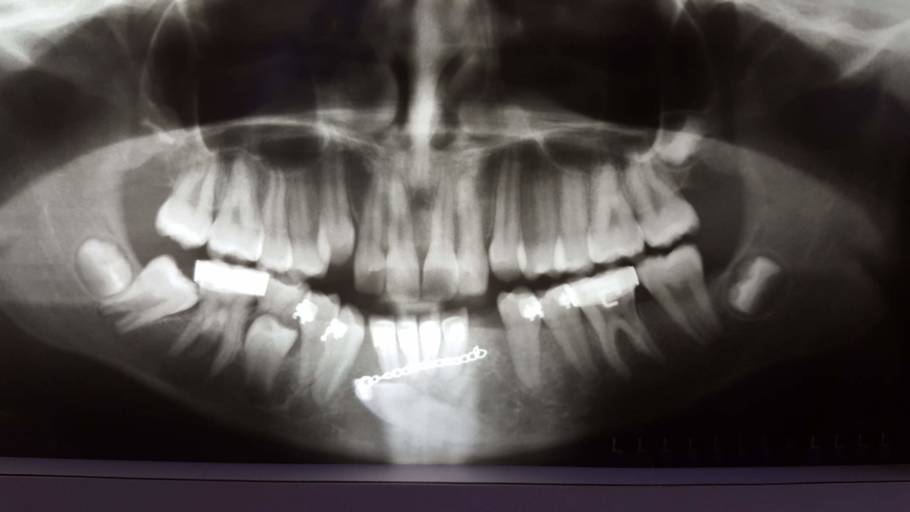

What can this be?

I went for a wisdom tooth removal but they found this space under tooth #24 after doing my X-ray examination.. I’m really scared that I might loose the tooth or have to have a tooth removed. I don’t have any pain with the tooth and no problems as to bleeding gums or any pain at all. I need some insight on what this could be? Or what’s going to happen next to this actual tooth..

I went for a wisdom tooth removal but they found this space under tooth #24 after doing my X-ray examination.. I’m really scared that I might loose the tooth or have to have a tooth removed. I don’t have any pain with the tooth and no problems as to...